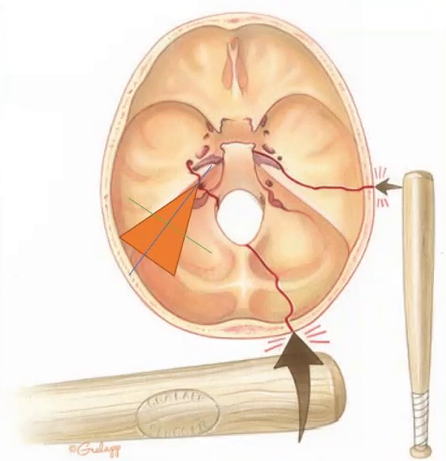

Os traumas temporais são divididos conforme orientação das linhas de fraturas ao EIXO PIRAMIDALdo osso temporal.

• Longitudinal (linha azul)

• Transversal (linha verde)

• Mista (cominutiva)

• Fragmentada

Mecanismos:

• Batida LATERAL geralmente gera fratura LONGIDUDINAL.

• Batida frontal ou OCCIPITAL (anteroposterior ou vice-versa) gera geralmente fratura TRANSVERSAL. Costuma requerer alta energia pra acontecer.